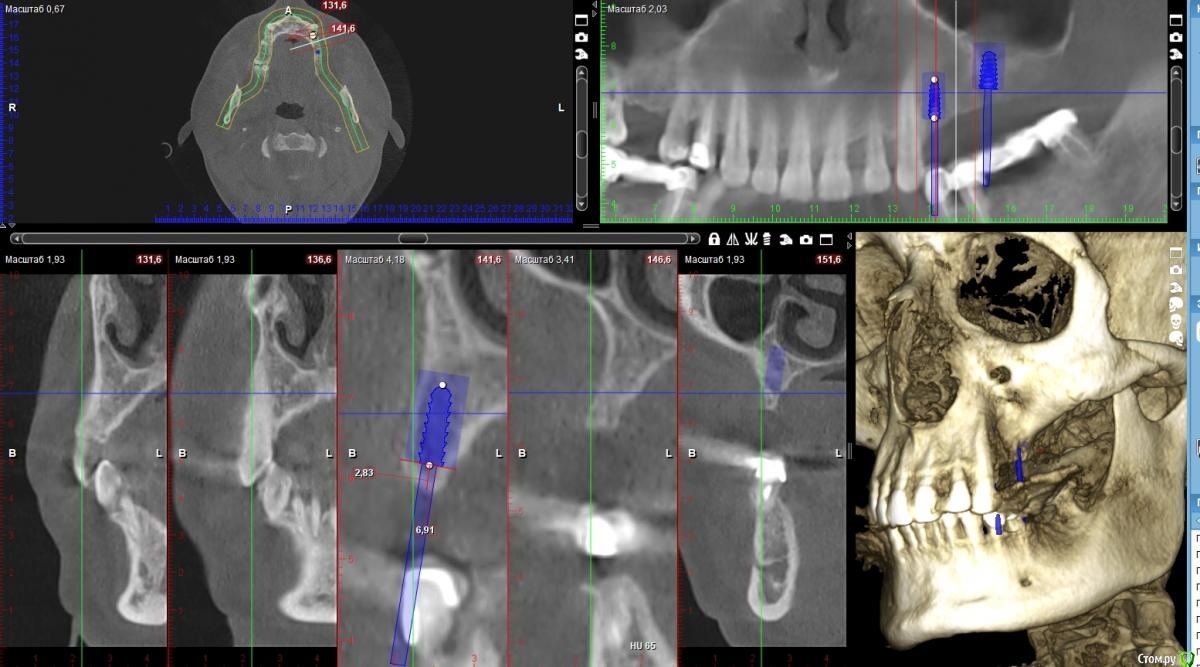

zumanok Опубликовано 28 октября, 2020 Поделиться Опубликовано 28 октября, 2020 Здравствуйте коллеги, обратился пациент с потерей зубов в результате пародонтита. В ходе лечения терапевту удалось улучшить гигиену пациента и на данный момент изменений нет два года. Пациент обратился с вопросом о имплантации. Планирую сделать мост 14-16 Возник вопрос, в области 16 есть возможность установить импл. 4.5 на 10, но от платформы до антагониста получается 14мм. стали бы Вы делать имплантацию без НКР ( что я и хочу сделать) или все таки делать НКР ПТФе мембраной? Благодарю за ответы. Ссылка на комментарий